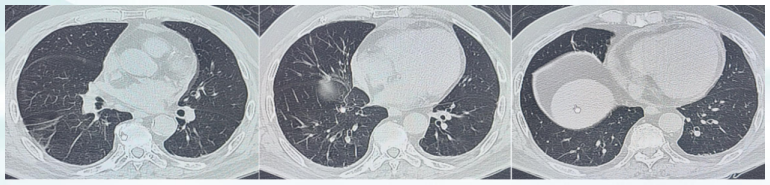

• 胸部CT(图1):双侧胸廓对称,双肺散在实性结节、部分密度较高,大者直径约0.5 cm,双肺散在条索影,左肺下叶见局限肺不张影;双侧支气管开口通畅;纵隔结构居中,心外形不大,心包增厚,冠状动脉见钙化影。纵隔内未见异常增大淋巴结;双侧胸膜增厚。诊断:双肺微结节,部分为硬结钙化灶,考虑左肺下叶少许炎症,双肺条索,心包积液,冠状动脉硬化,双侧胸膜增厚。

图片

1  患者入院胸部CT(2023-12-11)